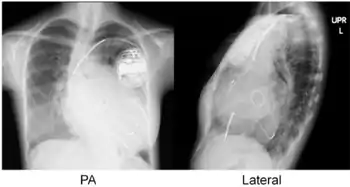

Cardiac resynchronisation therapy (CRT or CRT-P) is the insertion of electrodes in the left and right ventricles of the heart, as well as on occasion the right atrium, to treat heart failure by coordinating the function of the left and right ventricles via a pacemaker, a small device inserted into the anterior chest wall.[1]

CRT requires the placement of an electrical device for biventricular pacing, along with placement of (at least) two pacing leads, to facilitate stable left ventricular and right ventricular pacing. For all elements, the first stage of the process is local anaesthetic followed by incision to allow for approach from the appropriate vein. From here, the leads and device can be inserted.[1]

The device is inserted in a subcutaneous pocket created by the surgeon, the choice of left or right side of the chest wall is determined mainly by the patient's preference or location of preexisting device. The device, similar to that of a traditional pacemaker, is generally no larger than a pocket watch and has inserts for the electrode leads.[1]